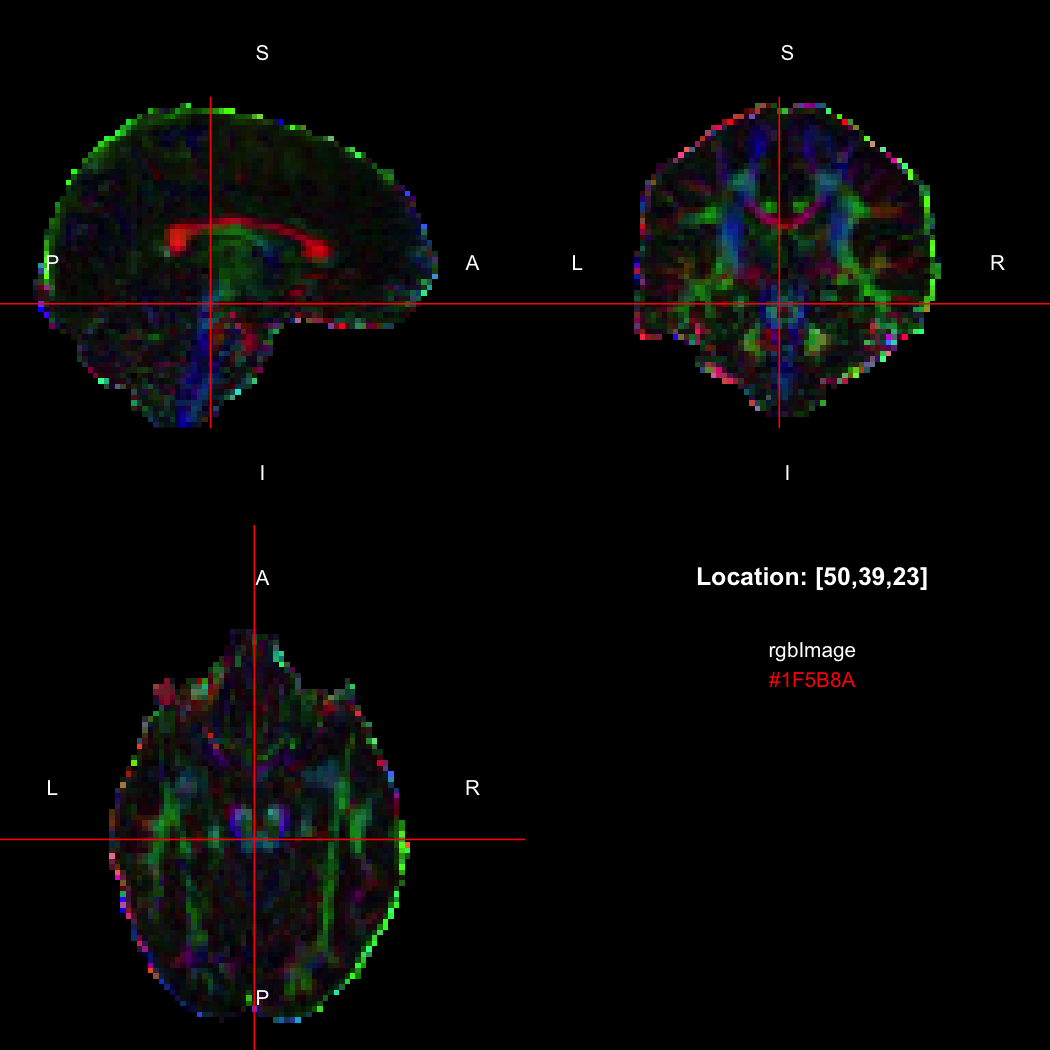

The package contains a basic image viewer, which can be used interactively or noninteractively to examine 2D or 3D images.

view(image)

By default, the viewer shows labels indicating image orientation, crosshairs pinpointing

the currently selected location, the numerical indices of the current

location, and the value of the image at that location. Options allow

each of these to be turned off, for the content of the bottom-right

panel to be customised entirely, for the colour scale to be changed, and

for additional images to be layered on top of the base image. See

?view for details.

## [1] 300+0iR’s native representation for RGB values is CSS-style hex

strings of character mode, which are reasonably space-efficient (8

or 10 bytes per value) but a little clunky to work with. For efficiency

of interchange between R and the NIfTI-internal datatypes,

RNifti uses a byte-packed representation of integer mode

instead, which takes up 4 bytes per value. Of course, the viewer

understands this format.

rgbImage <- readNifti(system.file("extdata", "example_rgb.nii.gz", package="RNifti"))

print(rgbImage)

## Image array of mode "integer" (2.1 Mb)

## - 96 x 96 x 60 voxels

## - 2.5 x 2.5 x 2.5 mm per voxel

class(rgbImage)

## [1] "niftiImage" "rgbArray" "array"

view(rgbImage)

Notice that values are shown in the viewer using R’s conventional hex

string format, but the data is of class rgbArray. The

function of the same name can be used to create these arrays from

strings or channel values, for the purposes of building RGB images from

data, while the as.character method and

channels function perform the opposite conversions.

as.character(rgbImage, flatten=FALSE)[50,39,23]

## [1] "#1F5B8A"

channels(rgbImage, "red")[50,39,23,1]

## red

## 31RGB images with an alpha (opacity) channel are also supported.